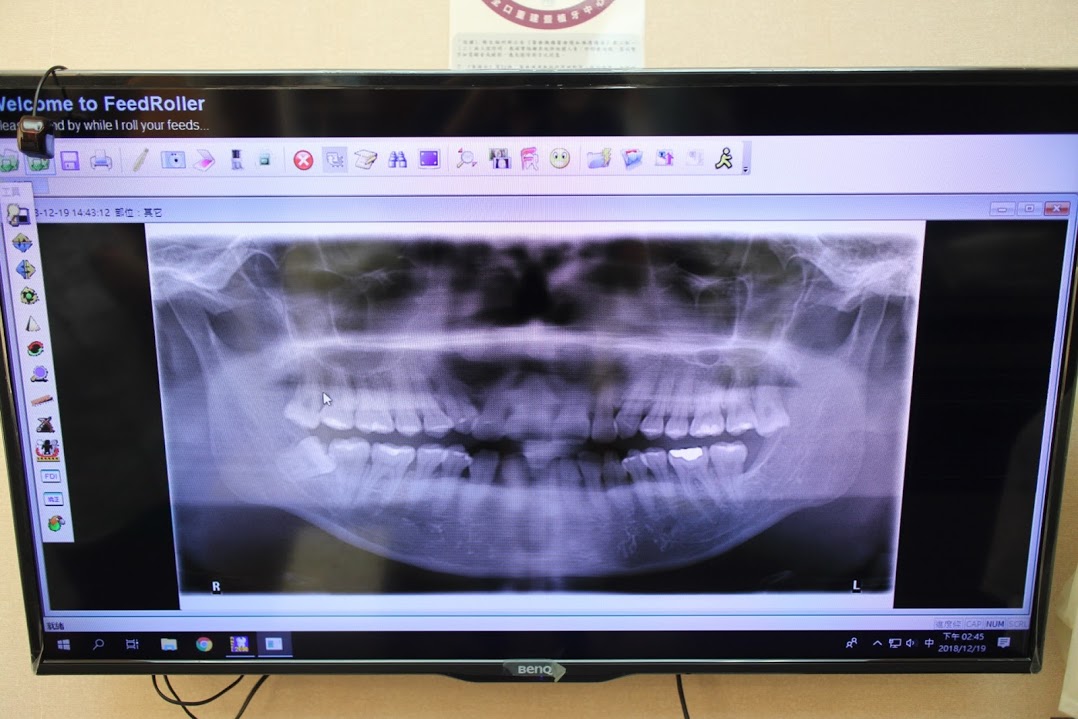

專業中壢牙齒健檢-牙齒X光照拍攝

這台3D電腦斷層掃描設備,不用像以前拍X光需要難受的塞東西到嘴巴深處

只要輕輕咬著就能拍攝整個口腔的X光照,讓照X光變得不再可怕

透過3D立體電腦斷層,可清楚了解患者的口內狀況,為牙醫師參考的輔助利器,針對患者狀況給予最好的治療建議。由不同角度檢查每顆牙齒,呈現骨頭360度立體3D影像。

傳統2D平面全口X光片僅能就2D平面影像觀察口內狀況,無法以立體的觀點做評估。

從照片可以看到像是長橫了的智齒、蛀牙、每顆牙齒深度、角度等都拍很清楚呢!